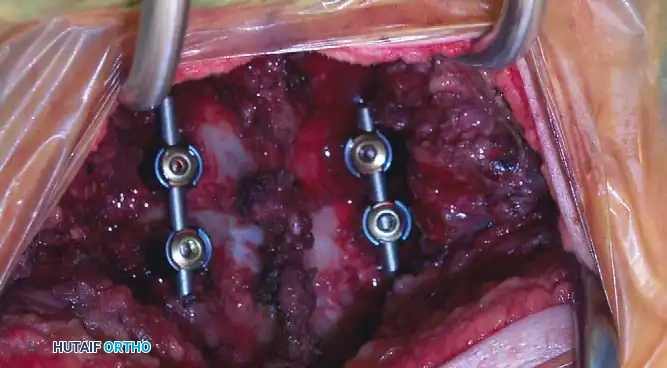

Anterior Cervical Discectomy and Fusion (ACDF)

Indications: Anterior column compromise, extruded traumatic disc herniations, or as the first stage in a 360-degree fusion for severe distractive flexion injuries.

Positioning & Approach:

* The patient is positioned supine on a radiolucent Jackson table.

* The neck is maintained in neutral alignment using Gardner-Wells tongs with 5-10 lbs of maintenance traction.

* A standard Smith-Robinson transverse incision is made, typically left-sided to avoid the recurrent laryngeal nerve (which has a more predictable course on the left).

* The avascular plane between the visceral axis (trachea/esophagus) medially and the carotid sheath laterally is developed.

Surgical Steps:

1. Exposure: Retract the longus colli muscles laterally to expose the anterior vertebral bodies and the damaged disc space.

2. Discectomy: Perform a complete discectomy using curettes and pituitary rongeurs. In trauma, the PLL is often torn; carefully remove any extruded disc fragments compressing the cord.

3. Endplate Preparation: Decorticate the cartilaginous endplates using a high-speed burr to expose bleeding subchondral bone, ensuring a robust fusion bed.

4. Grafting: Insert a structural allograft or PEEK cage packed with autograft/demineralized bone matrix (DBM) into the disc space.

5. Plating: Apply a rigid anterior cervical plate. Ensure screws are placed parallel to the endplates and do not breach the adjacent disc spaces.

Fig 6. Anterior cervical plating construct providing rigid stabilization of the anterior column.